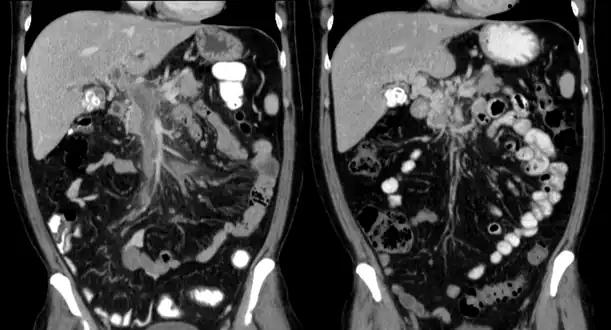

Computed tomography scan showing portal vein thrombosis (with cavernous change of portal vein ) -

Portal vein thrombosis on computed tomography (left) and cavernous transformation of the portal vein after 1 year

The diagnosis of portal vein thrombosis is usually made with imaging confirming a clot in the portal vein; ultrasound is the least invasive method and the addition of Doppler technique shows a filling defect in blood flow. PVT may be classified as either occlusive or nonocclusive based on evidence of blood flow around the clot.[5] An alternative characterization based on site can be made: Type 1 is limited to the main portal vein, Type 2 involves only a portal vein branch (2a, or 2b if both branches are affected), and Type 3 if clot is found throughout both areas.[8] Determination of condition severity may be derived via computed tomography (CT) with contrast, magnetic resonance imaging (MRI), or MR angiography (MRA). Those with chronic PVT may undergo upper endoscopy (esophagogastroduodenoscopy, EGD) to evaluate the presence of concurrent dilated veins (varices) in the stomach or esophagus.[3] Other than perhaps slightly elevated transaminases, laboratory tests to evaluate liver function are typically normal.[1] D-dimer levels in the blood may be elevated as a result of fibrin breakdown.